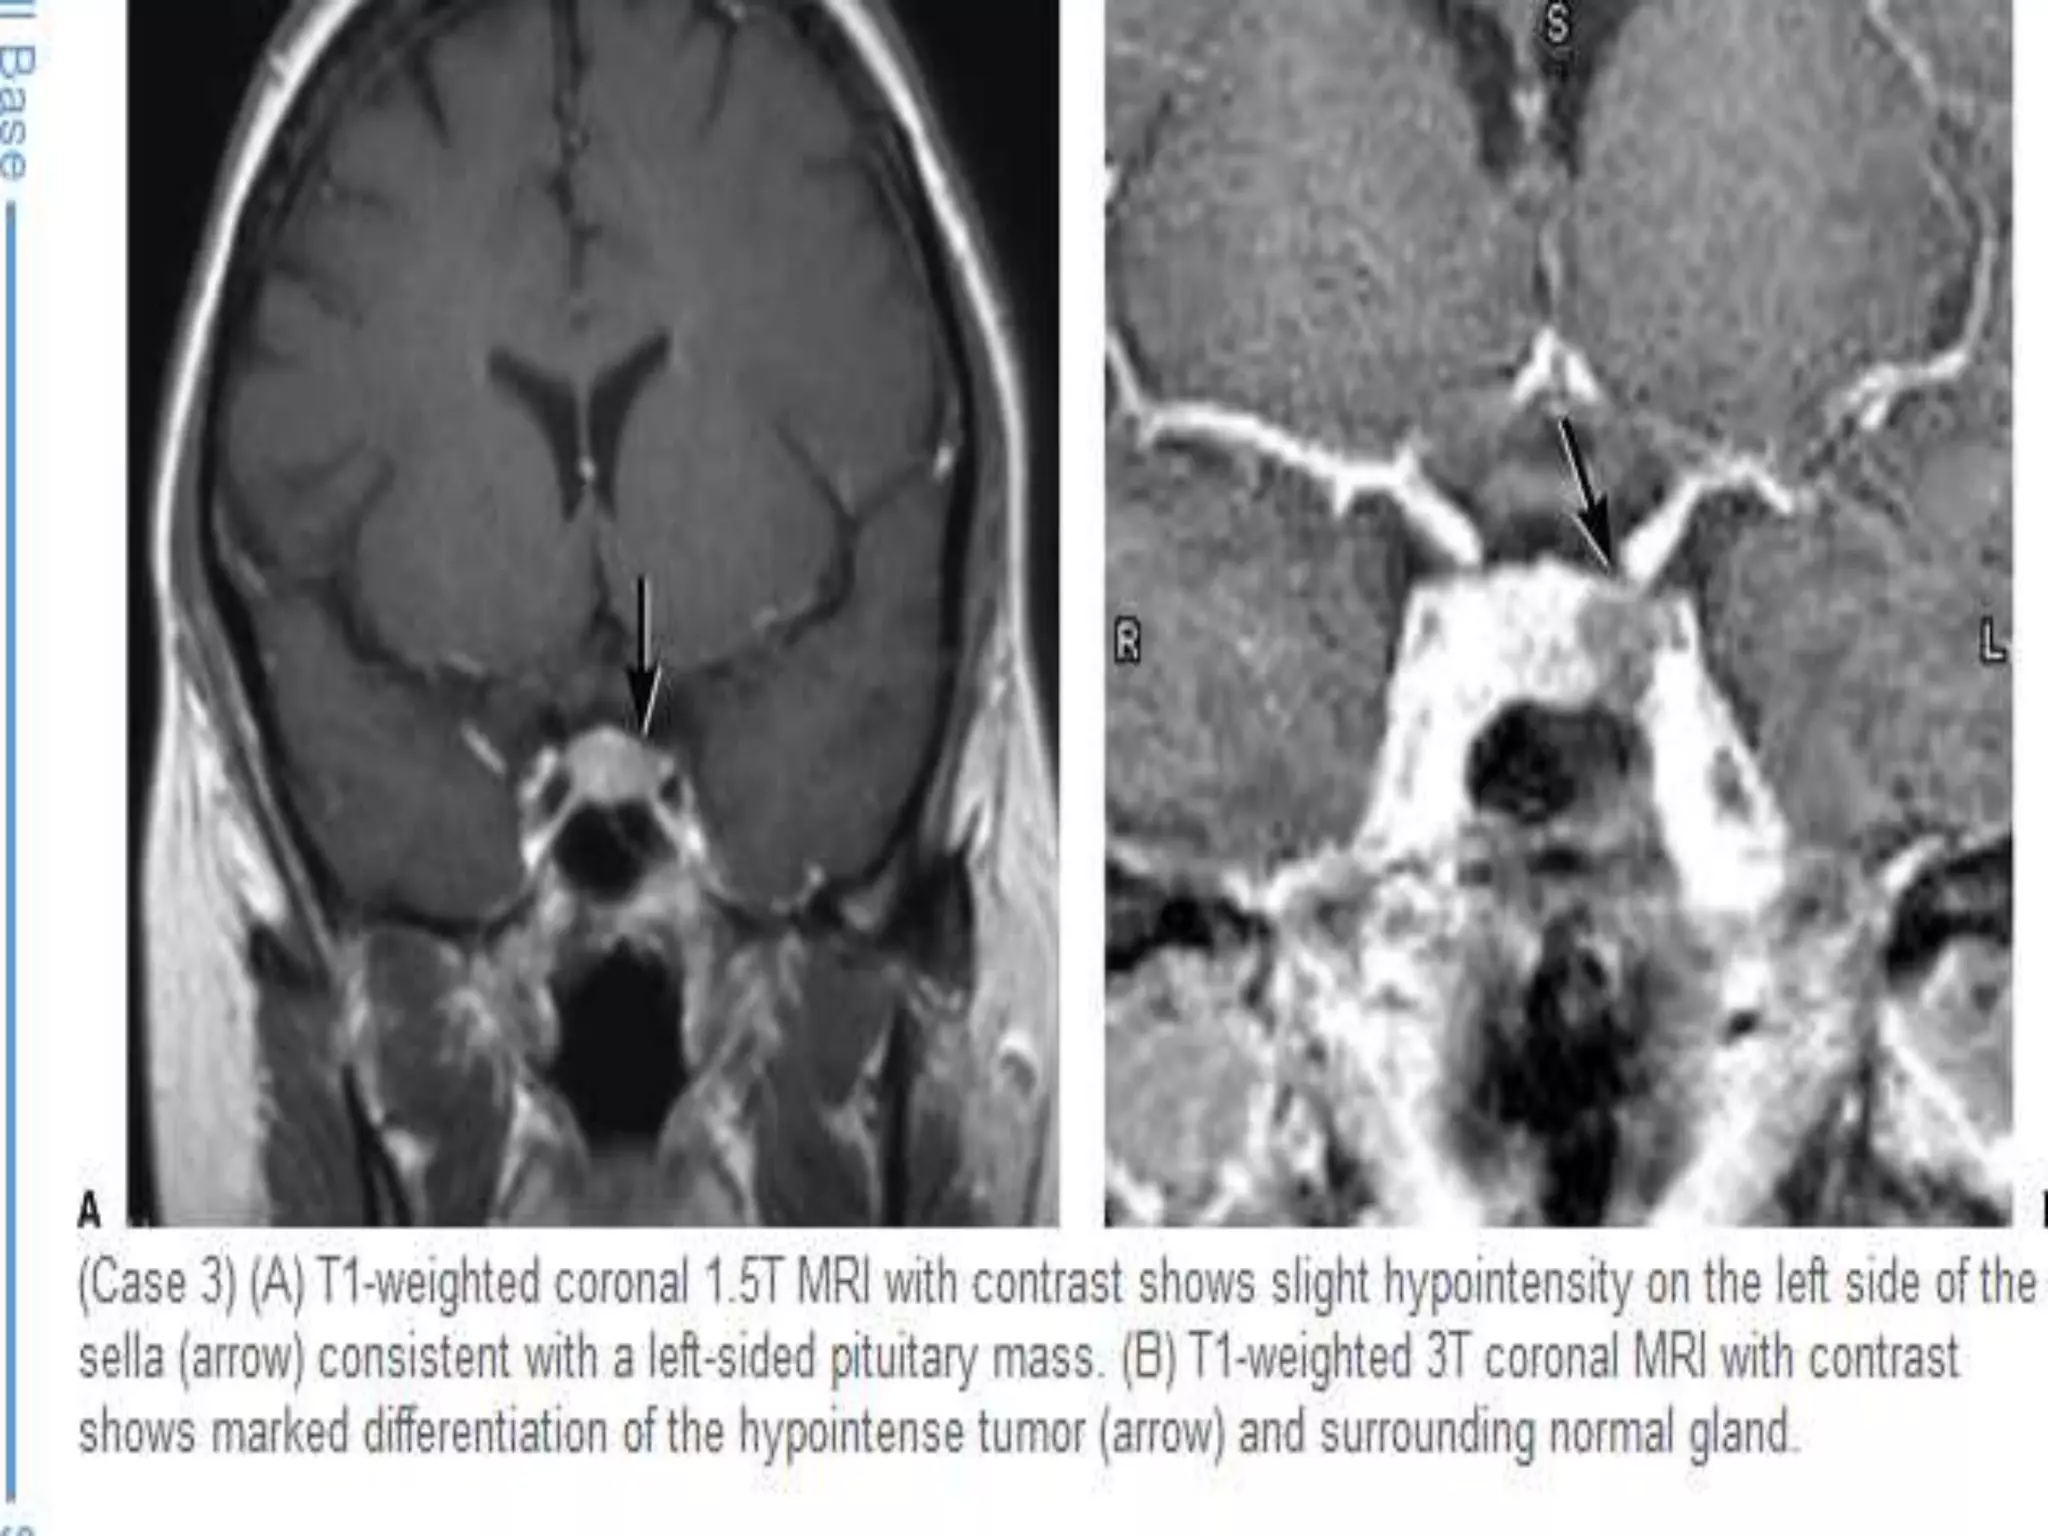

Coronal T1 and T2-weighted images and T1-weighted images before and after gadolinium. In

this patient the lesion in the pituitary gland is only detectable after the administration of

intravenous contrast. The differential diagnosis: pituitary microadenoma or Rathke's cleft cyst.